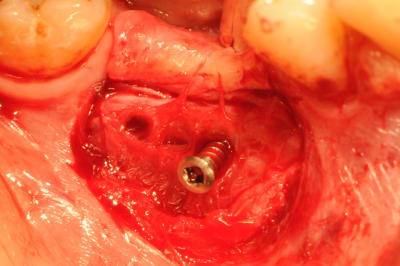

photo 6-7-8 : retrait des vis FAST ayant servi de piquet de tente à la ROG

Sur la photo vis en place : elle est déjà un peu dévissée, ou il y a eu 2 mm de perte du matériaux ? ( c'est ce que j'ai eu aussi les deux fois ou j'ai fait cette technique ).

En effet si on compare la photo de ton post initial par rapport à la photo de la réouverture, on peut voir que la vis dépasse toujours autant par rapport au niveau osseux initial.

pour clio et jeff, la photo montrant la vis est trompeuse et je comprends mieux vos réactions.

en fait elle n'était pas dans sa position initiale car j'ai fait la photo avec la vis ayant été retirée à moitié.

photos 1 et 2 mise en place des vis et comblement osseux.

photo 3 et 4 le niveau osseux n'a pratiquement pas bougé.